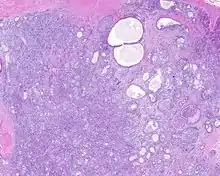

High power H&E stained image of a parotid sclerosing polycystic adenoma with eosinophilic granules

When reviewed by a pathologist, the findings are quite similar to fibrocystic changes of the breast, although they are different enough, that it is now recognized to actually represent a true neoplasm (clonal proliferation) through various studies.[5] Specifically, the lesions are usually well-circumscribed, containing lobules of haphazardly arranged ducts, myoepithelial cells, and acini that have abundant sclerosing or hyalinized fibrosis. Apocrine change is quite common in the ductal cells.[6] The ducts range from small ductules to cystically dilated spaces (more than 4 striated duct-widths across), often containing products of secretion or reactive histiocytes. A very curious and characteristic finding in all of the lesions is the presence of bright pink (eosinophilic) acinar granules (which are altered zymogen).